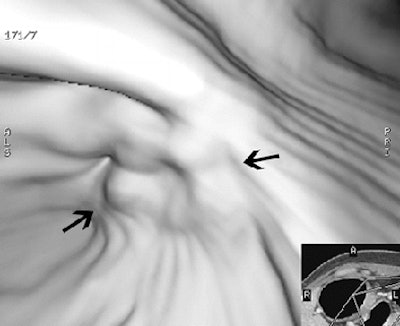

| Early gastric cancer in a 33-year-old woman. There is no identifiable gastric wall thickening on either the transverse CT scan (a, above) or the coronal MPR image (b, below). Virtual endoscopic image (c, bottom) shows a shallow depressed lesion with surrounding mucosal nodularity (arrows) in the angle of the stomach, suggesting early gastric cancer (T1). At histopathologic analysis, this lesion was diagnosed as type IIb + IIc early gastric cancer (pT1). Images used with permission of the Radiological Society of North America (Radiology 2005 Sep;236(3):879-85). |